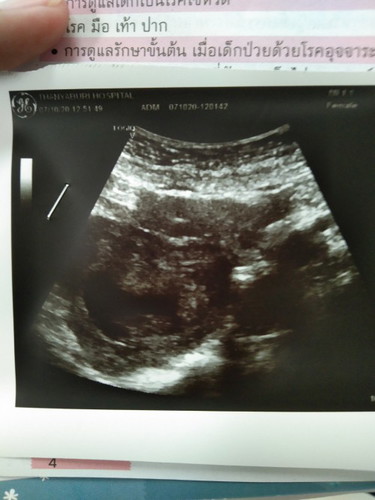

พอดีนับอายุครรภ์เองได้11w หมอซาวด์ดูบอกว่าแค่8wยังเห็นแค่หัวใจน้อง เรากลัวน้องจะเป็นอะไรควรไปซาวด์แบบละเอียดมั้ยคะ เพราะแม่เป็นไฮเปอร์ด้วยกังวลมากค่ะ

หมอจะนับจาก ปจด เกือนสุดท้ายที่เรามาวันแรก ค่ะ ถ้าเราเป็นสม่ำเสมอ แล้วบอกหมอตรงจริง หมอจะคำนวนออกมาได้ตรงกว่าเราค่ะ ส่วนในใบซาวมันบอกจากขนาด ณ ตอนนั้นค่ะว่าขนาดประมาณนี้คือเท่าไหร่ เราต้องอิงตามหมอคำนวนค่ะถึงจะรู้ว่า ตกเกณฑ์หรือพอดีเกณฑ์หรือมากกว่าเกณฑ์ค่ะ ของเราใบซาวไม่เคย ซ้ำกันสักครั้งๆขึ้นๆลงๆค่ะ และสัดส่วน แต่ละส่วนของลูกก็ใหญ่เล็กไม่เท่ากัน แถม นน ขึ้นมากกว่าเกณฑ์เสมอ